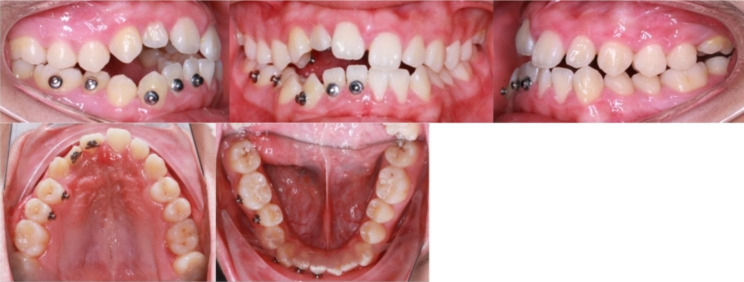

The proband was still in the peak of growth at the first visit; after a year of observation, it was found that the open bite was increasing. We made local traction to the impacted teeth. Bonding lingual button at the palatal surface of #11,#12,#14,#15 and the labial surface of #41,#42,#43,#45,#46 (Fig. 4). It was followed by vertical intermaxillary traction with rubber bands between the upper and lower buttons.

Fig. 4.

Intraoral photographs during treatment

After six months of traction, the open-bite of the anterior tooth area did not reduce. We used Mimics 15.0 to convert CBCT data into 3D models before and after orthodontic treatment and superimposed them to evaluate the three-dimensional movement of the impacted teeth. The results showed that only the third molars grew, while the anterior teeth barely moved (Fig. 5). At one year recall, we found that the degree and range of open-bite in the anterior and posterior dental areas further increased (Fig. 6).